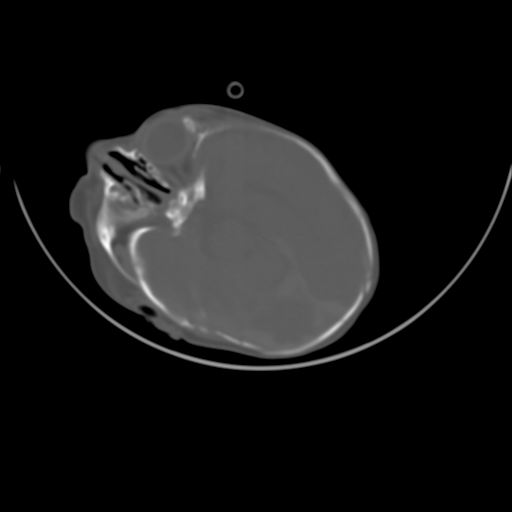

双侧硬膜下血肿并蛛网膜下腔出血。

双侧硬膜下血肿并蛛网膜下腔出血

硬膜下及蛛网膜下腔出血。

hie 蛛网膜下腔出血,硬膜下血肿。

hie;双侧硬膜下血肿并蛛网膜下腔出血

hie,双侧硬膜下血肿并蛛网膜下腔出血

双侧硬膜下血肿并蛛网膜下腔出血,考虑维生素k缺乏引起.

较大范围出血,应考虑维生素k缺乏引起,结合临床吧。

好像脑实质没有明显低密度影,各位大侠怎么支持hie呢?